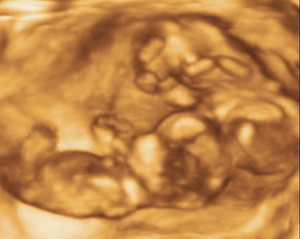

Andriska és Bernike